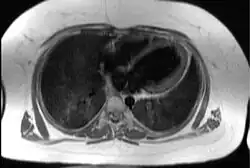

| Transaxial image of the chest at the level of the heart illustrating the typical degree of subcutaneous and epicardial adipose tissue (shown in white) in a patient with Alström syndrome; hence the difficulty in imaging by echocardiography | |